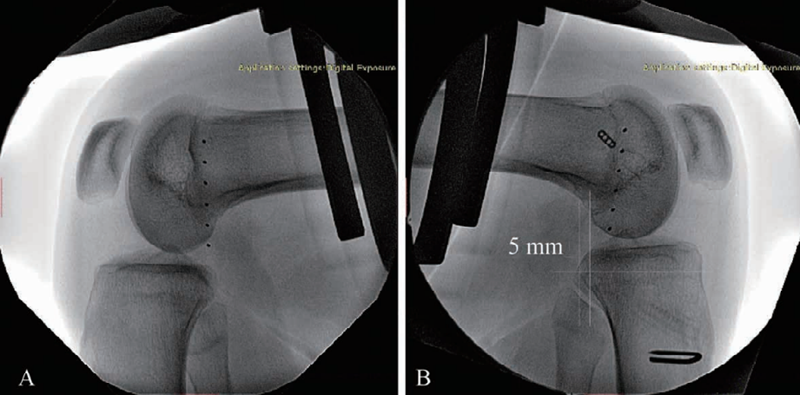

后方应力位或跪位X线检查是诊断PCL损伤的可靠方法(图6),对比健侧,后移增加0~7mm为PCL部分损伤(图7),8~11mm为单纯PCL全部断裂(图8),12mm以上可能为PCL和PLC等其他结构合并损伤(图9)。

图7 PCL部分损伤X线影像

应力位X线片(B)示胫骨后移超过健侧(A)5mm

图8 PCL完全断裂X线影像

应力位X线片示患侧(B)胫骨后移超过健侧(A)10.1mm

图9 PCL完全断裂合并PLC损伤X线影像

应力位X线片示患侧(B)胫骨后移超过健侧(A)13.5mm